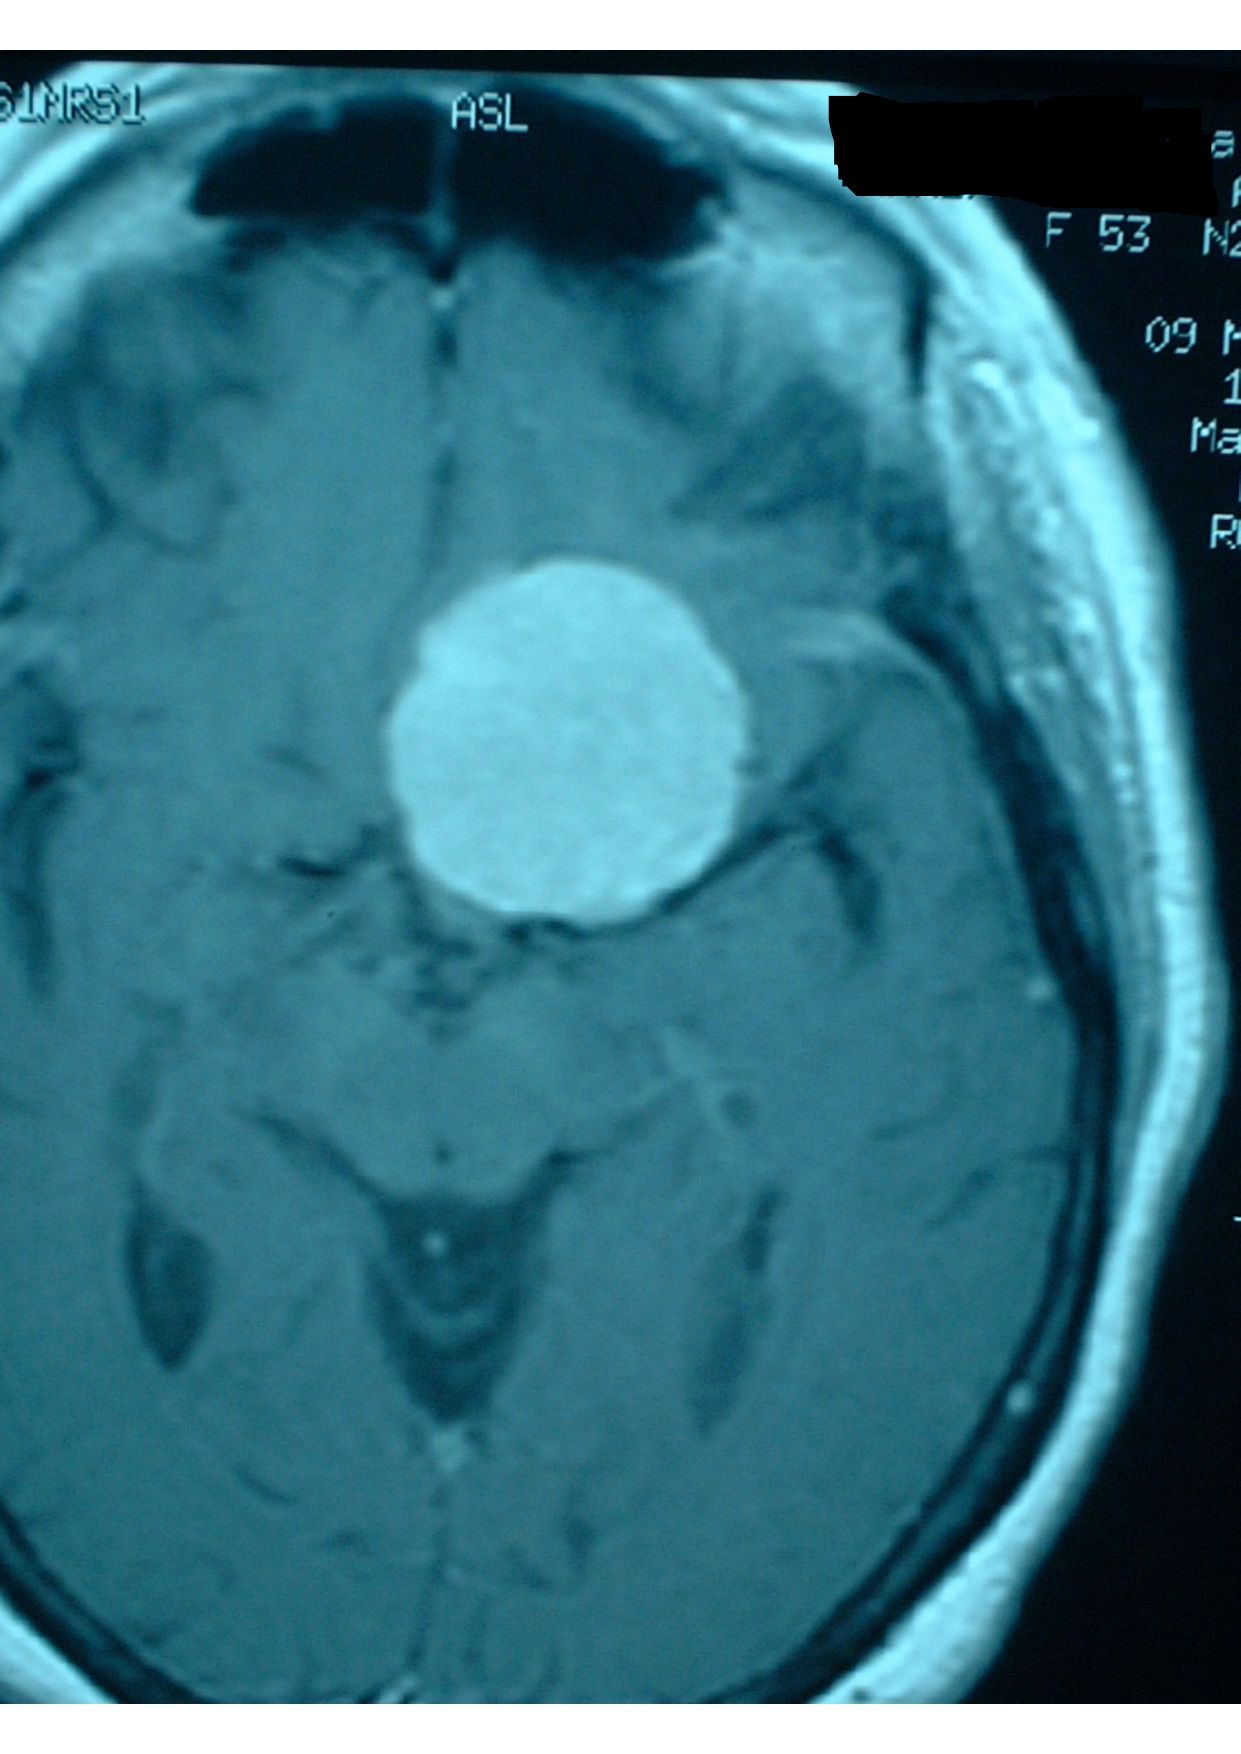

Patologias Tumoral Crânio Encefálica e Raquidiana

- Diagnóstico e tratamento de tumores que afetam o cérebro e a coluna vertebral.